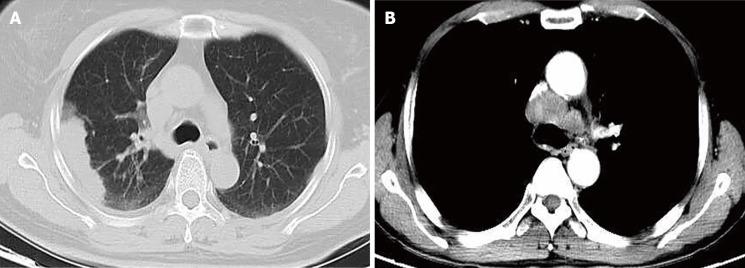

All clinical data of six patients with confirmed PEAC from 2013 to 2018 were collected, and data on diagnosis, differential diagnosis, and treatment of PEAC are discussed combined with all the associated literature. The mean age of six patients was 64.0 ± 5.6 (59-73) years old. Their clinical manifestations were heterogeneous, and during their disease course, there were no gastrointestinal symptoms. There was no evidence from colonoscopy or imaging studies to suggest digestive tract tumors or new metastases. The most commonly mutated gene was (50.0%), and the pathological features of the six cases were similar to those of colorectal cancer. CDX2 (83.3%) and CK7 (66.7%) had the highest positive rates upon immunohistochemical examination. In the associated literature, 252 cases were identified, and the most commonly mutated gene was (42.9%). Additionally, CDX2 (68.3%) and CK7 (85.8%) had the highest positive rates. Patients mainly received surgery, chemotherapy, and radiotherapy, immunotherapy was not included.

Positive results for CDX2 and CK7 play an important role in the diagnosis and differential diagnosis of PEAC, and immunotherapy or targeted therapy focused on needs to be further studied for the treatment of PEAC.